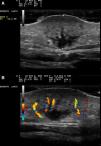

En la consulta de dermatología se realizó una ecografía cutánea de la lesión. Mediante una exploración en modo B (sonda 18MHz Esaote MyLab™25Gold©) se objetivó la presencia de un nódulo dérmico de 20×15×11mm, con extensión al tejido celular subcutáneo en profundidad. Este presentaba un contenido heterogéneo y no encapsulado, con delimitación de bordes poco definidos (fig. 2A). De forma llamativa la lesión presentaba mayor hipoecogenicidad en el plano más superficial o dérmico y en el plano más profundo o hipodérmico, encontrándose ambos separados por un plano más hiperecoico a través del cual se observaban trayectos tubulares hipoecoicos. La exploración en modo Doppler color reveló la presencia de intensa neovascularización con vasos intratumorales de gran tamaño (fig. 2B).

A. Ecografía en modo B, 18MHz. Nódulo dérmico con extensión a tejido celular subcutáneo, contenido heterogéneo y con bordes poco definidos. Planos superior y profundo con mayor hipoecogenicidad respecto a plano intermedio. B. Ecografía en modo Doppler color mostrando vasos intratumorales de gran calibre.